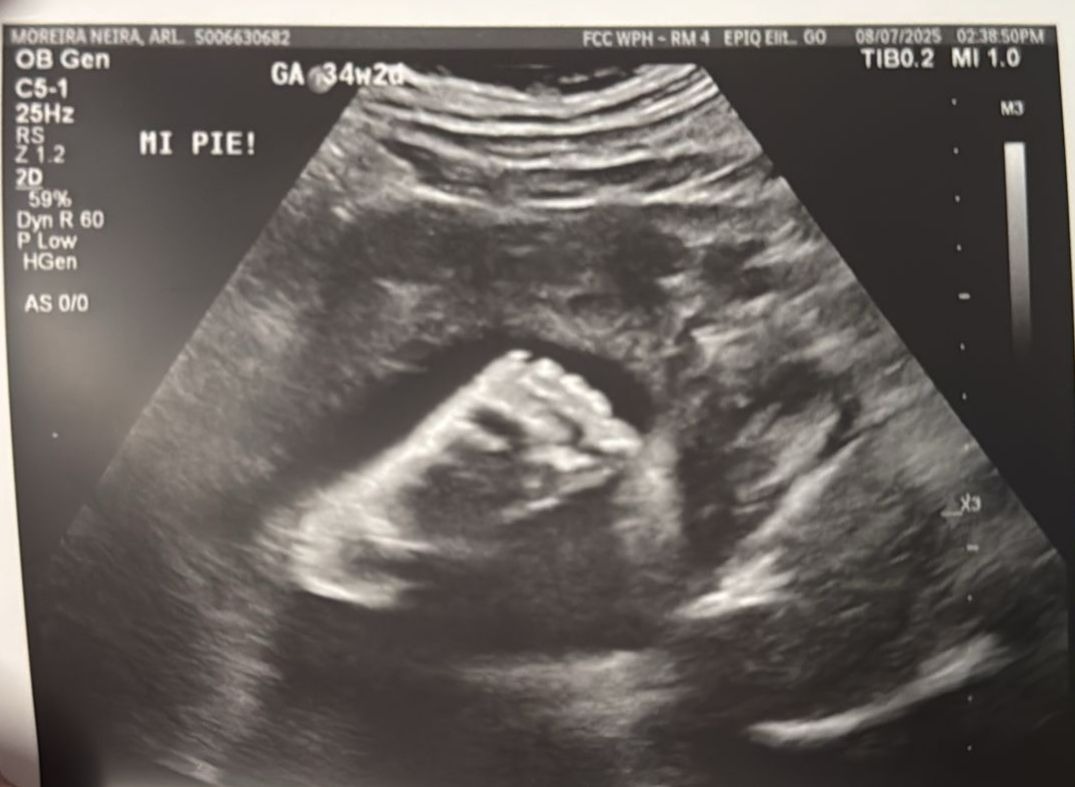

Hello, my name is Ariana Moreira, and I am going through the most challenging pregnancy of my life. My baby Emma is on her way with a complex heart condition that requires continuous medical monitoring and possible interventions as soon as she is born.

Emma has been diagnosed with Heterotaxy and a single-ventricle heart.

Although science has advanced greatly, there are still many things that cannot be detected until after she is born. Every day is filled with uncertainty, holding onto faith and hope as we wait for the next steps her doctors will need to take.